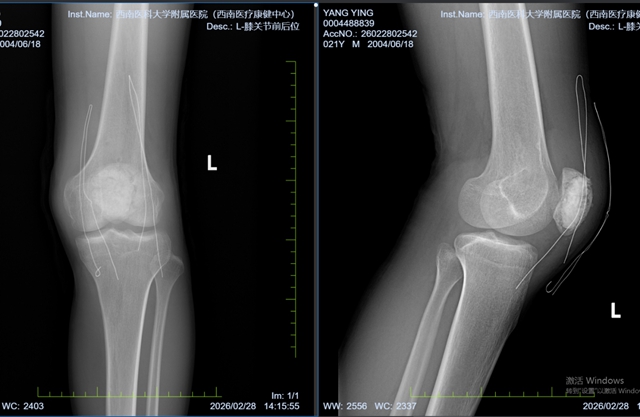

图3:术后的膝关节x片